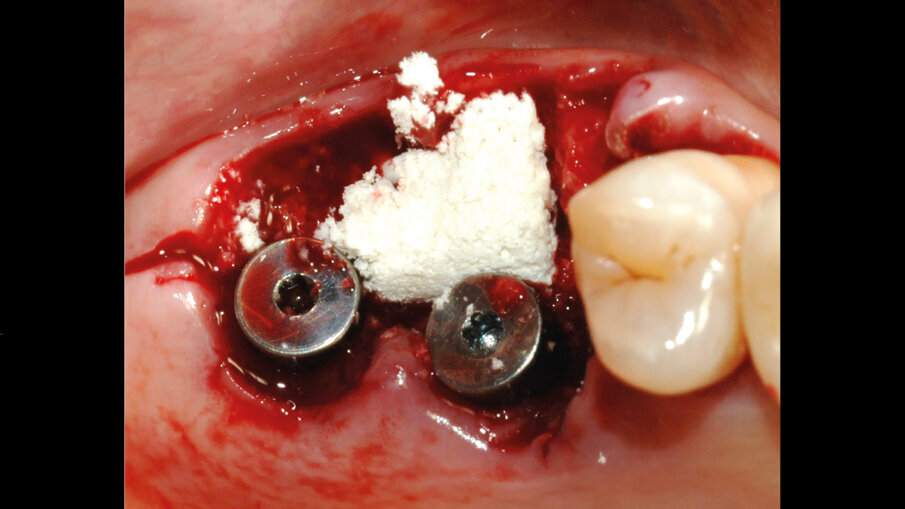

Per colmare il gap tra impianti e osso si eseguiva un mantenimento alveolare a livello dello spazio lasciato vuoto in seguito all’estrazione delle radici vestibolari mediante l’impiego del cilindro di pasta ossea liofilizzata (Fig. 5). La pasta ossea liofilizzata, una volta idratata con il sangue intra-operatorio del paziente, diventava malleabile e andava a colmare perfettamente i difetti peri-implantari. L’innesto veniva ricoperto con la matrice collagenica tridimensionale che garantiva una protezione di 2-4 settimane oltre a costituire il substrato adatto alla proliferazione dei fibroblasti e favorire la guarigione dei tessuti molli attorno agli impianti (Figg. 6, 7). Venivano applicate le viti di guarigione e i lembi venivano chiusi con delle suture in Monomyd 5-0 per favorire la guarigione per seconda intenzione (Fig. 8). L’RX post-operatoria confermava il corretto posizionamento implantare (Fig. 8). Dopo l’intervento, il paziente seguiva una terapia domiciliare a base di amoxicillina ac. clavulanico 875/125 mg: 1 compressa ogni 12 ore per 7 giorni. In aggiunta, nimesulide per i primi 2 giorni. A livello della sede operata, venivano prescritto un gel a base di Clorexidina da applicare 2 volte al giorno, per 10 giorni. Ad un mese dalla procedura chirurgica, l’aspetto clinico mostrava il buon procedere del processo di guarigione dei tessuti molli. A sei mesi di distanza si osservava una completa maturazione dei tessuti perimplantari (Fig. 9). Venivano quindi prese le impronte e successivamente consegnate le protesi provvisorie a carico degli elementi 26, 27. Tre mesi più tardi, dopo aver raggiunto la completa maturazione dei tessuti duri e molli, previa impronta analogica, venivano realizzate le protesi definitive. L’RX di controllo mostrava l’ottima integrazione degli impianti. La paziente era soddisfatta (Fig. 10).

Fig. 5 - Applicazione della pasta ossea liofilizzata (Bio-Gen Putty, Bioteck Spa) a secco. Si idrata con il sangue del paziente, diventando malleabile e adattandosi per riempire il gap tra impianto e osso alveolare. Avvitamento delle viti di guarigione.

; Fig. 6 - Matrice tridimensionale collagenica Xenomatrix (Xenomatrix, Bioteck Spa). Viene modellata a secco.

; Fig. 7 - Apposizione della matrice collagenica a ricoprire l’innesto osseo e favorire la crescita dei tessuti molli.